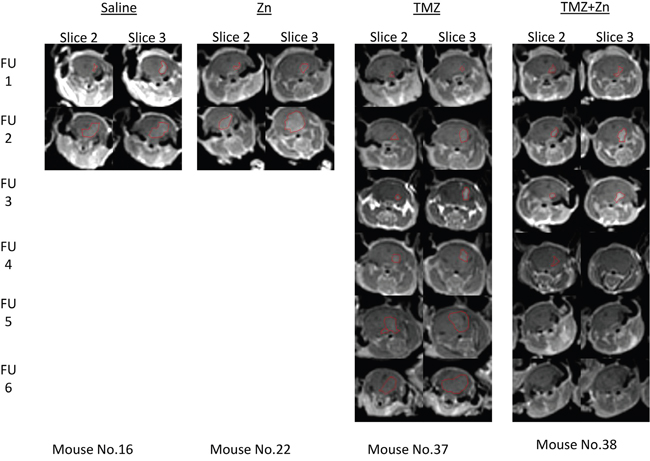

We explored the ability of orally administered TMZ and zinc to inhibit tumor growth in nude mice carrying intracranial implants of U87-MG cells compared to treatment with TMZ only, ZnCl2 only or PBS control. A total of 48 nude mice were stereotactically inoculated with 300,000 U87-MG cells each. After the first MRI, the mice were distributed homogenously into treatment groups according to tumor size. During treatment, five additional MRI scans were conducted in order to evaluate the effect of the treatment on tumor progression. Figure 4 illustrates representative MRI follow ups of one mouse in each treatment and the tumor region circled by red mark. For these, the tumor shrunk only in the mouse with the combined TMZ+ZnCl2 treatment.

Figure 4: Tumor detection by contrast enhanced T1-weighted MRI of xenograft mice. Tumor shrinkage is evident only as a result of ZnCl2 and TMZ combination treatment. The figure represents consecutive MRI scans follow ups (FU) of the same mouse with the specified treatment. Slices 2 and 3 are presented since they had the highest volume at the first MRI and also used for the follow ups. The region of interest (tumor) is indicated with red line.

ZnCl2 only or PBS treated animals developed substantial tumors from which they died or were terminated by humane sacrifice according to the institutional committee guidelines between 14 and 21 days after tumor cell implantation with no clear difference between these two groups. For TMZ treated mice, 75% of animals were alive after 28 days. 92% of animals treated with ZnCl2 in combination with TMZ were alive after 28 days, suggesting that ZnCl2 in combination with TMZ may be effective and tumor specific in this aggressive GBM model. In the combination treatment, two of the twelve mice showed no detectable tumor beginning with the third (ie at 21d) MRI and all following MRIs. These mice continued living beyond two months after the completion of the experiment. To investigate this effect further, we quantified the tumor volume. First, we compared the total tumor volume across treatment groups (Figure 5A) and (Supplementary Table S3). A significant reduction of tumor volume was observed at the time of the fifth MRI follow up, or 35d, in the combined TMZ and ZnCl2 treatment group compared with TMZ treated mice. The tumor volume in the combined treatment group remained steady and even completely disappeared in two mice whilst the tumors kept growing in the TMZ group. At the fifth time point, the tumor volume was significantly lower in the combined treatment group, compared to TMZ treated group (Fisher’s exact test p=0.038). Interestingly, at 6 weeks, the surviving mice undergoing the combined treatment were tumor-free while the tumors in the TMZ-treated mice were still growing. Unfortunately, only 2 mice survived in the combination arm, limiting our statistical analyses at this time point. A high mortality rate (5 mice out of 9) was observed in the TMZ+Zncl2 between the fourth and fifth MRI. Out of the 5 mice only 2 deaths could be associated with high tumor volume. The three other deaths were most probably due to the complications of gavage treatment since their tumor volume was low. Overall Six mice from the TMZ and ZnCl2 treated group and two mice from the TMZ group died regardless of the tumor size, during anesthesia or oral gavage procedure. Complications associated with gavage are known to lead to an increase in morbidity and mortality [27]. Next, we compared mean tumor volume across all treatments. Strikingly, the combination treatment resulted in attenuated tumor growth and even shrinkage in some cases whereas TMZ treatment alone resulted in tumor growth (Figure 5B). Finally, comparisons of the blood count and clinical biochemistry blood tests (creatinine, calcium, phosphorus, urea, glucose, bilirubin, total protein, albumin, globulin, cholesterol, alkaline phosphatase, SGOT, SGPT, sodium, potassium, chloride) were made between control groups and each treated group. No significant differences were found in any of the compared measurements. No gross morphological or structural changes, including edema, necrosis, inflammation, or pigmentation, were observed within all organs in the histopathology study suggesting the treatments were well tolerated in all groups (data not shown).